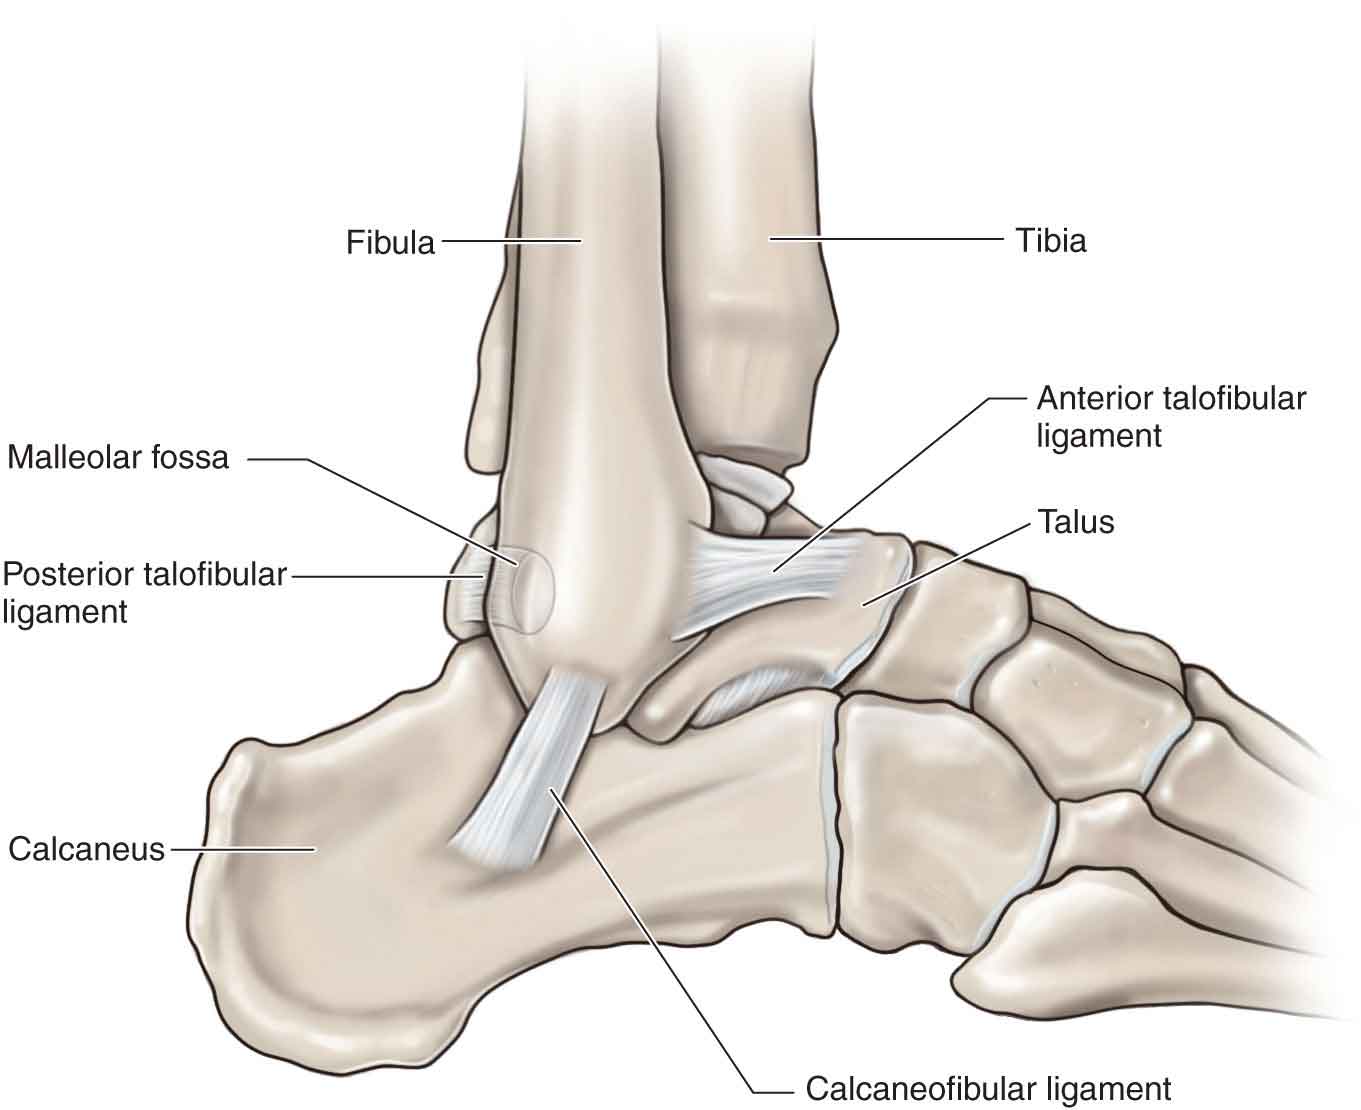

Анатомические фото голеностопного сустава и его суставных поверхностей